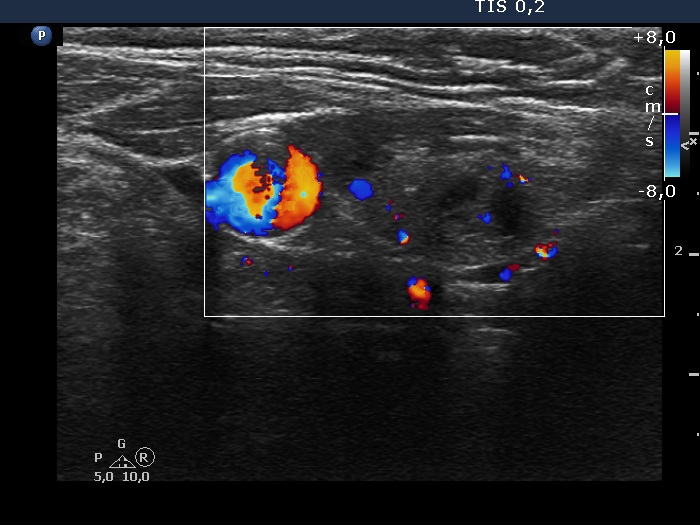

Right lobe, longitudinal scan

Lower part of the left lobe, transverse scan, color Doppler mode. The cystic nodule shows scanty blood flow.